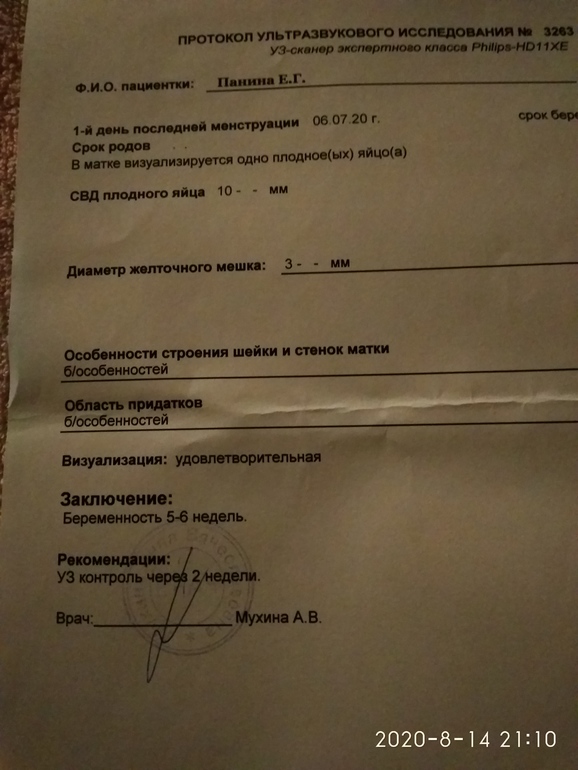

А, просто так написано) Я так понимаю эмбриончик еще не увидели? Размеры хорошие.

Рано, сегодня 21 ДПП , ездила чтобы убедиться ,что беременность маточная.